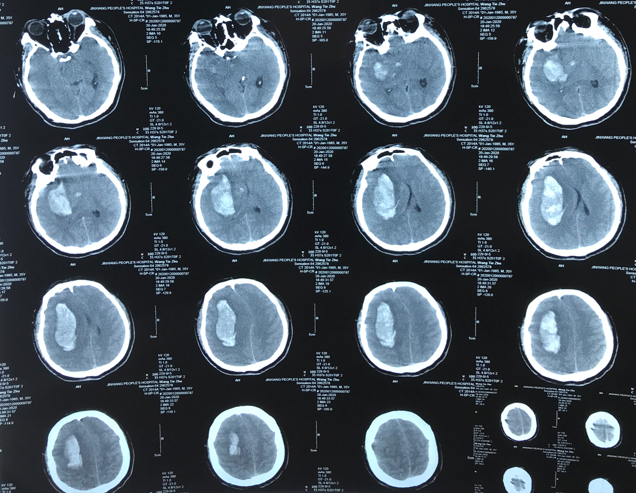

CT显示为右侧颞枕叶脑梗塞,同时累及了大脑中动脉和大脑后动脉分布区。

出血时CT: